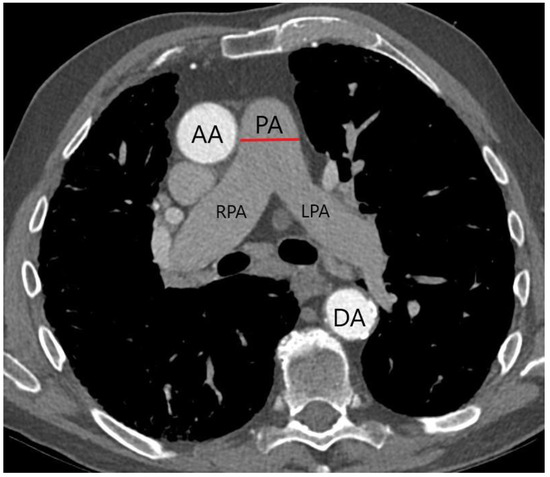

2.3. CTA Protocol and PA Diameter Measurement